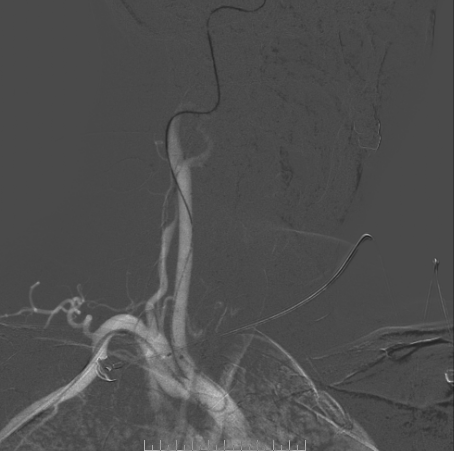

脑血管造影

左侧椎动脉造影

左侧颈总造影

右侧颈总造影:右侧大脑中动脉瘤